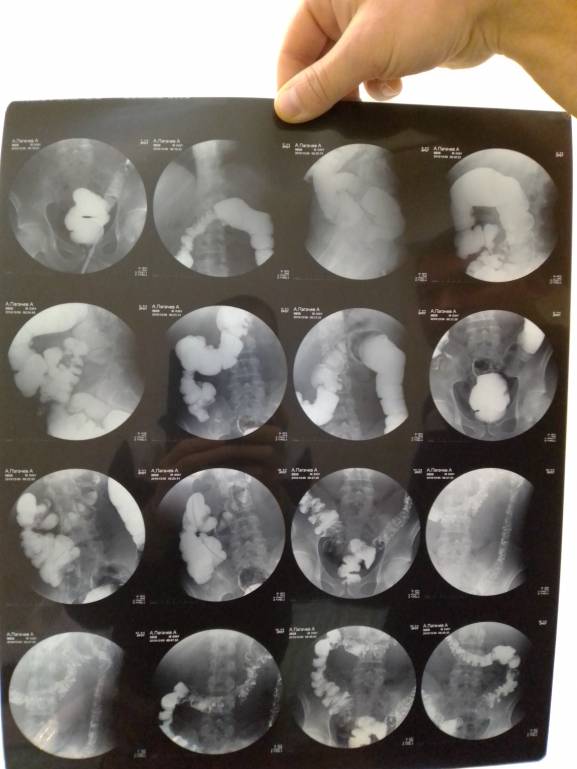

Деньги на лекарства - IMG_20200105_134627.jpg

Деньги на лекарства - IMG_20200105_134622.jpg

Деньги на лекарства - IMG_20200105_134550.jpg

Деньги на лекарства - IMG_20200105_134542.jpg

Деньги на лекарства - IMG_20200105_134444.jpg

Деньги на лекарства - IMG_20200105_134433.jpg